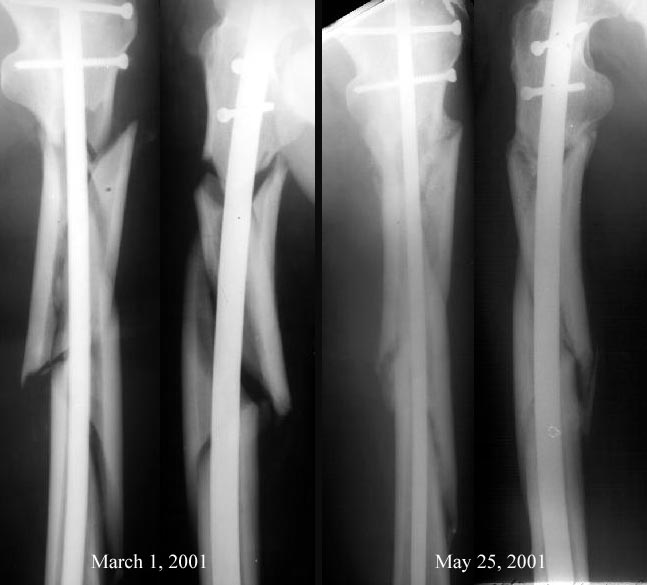

A first case of the closed subject has just been performed in our unit (guess who :-). The nail was a rectangular flat titanium plate 12 mm wide and 5 mm thickness (from a provision set for osteosynthesis by individually modelled nails according to a rather popular in Russia methodic of Zverev-Klyuchevky). It was only bent in sagittal plane and its ends were rounded. Cortical 4,5 mm titanium screws were used for locking performed as free-hand at both levels.

The case was selected because the whole isthus zone was comminuted and no reaming was required - no appropriate equipment is available. What was reached can be seen on attached x-rays.

From: chris wilson

The entry point of the nail is a little medial, so the most proximal fragment is in varus. That said, it's a pretty good position for such a difficult fracture, especially done closed. In our institution, the position would be deemed most acceptable, and we would be prepared to wait 3 months-if there was no callus at all then, we would bone graft it.

Alignment good, but one really needs to see the joint above and joint below to be sure. High probability of healing without additional surgeries especially if the fracture was not surgically opened and stripped of blood supply. This can be approached from supine position or with the patient in lateral decubitus position.

My prediction is that you'll see abundant callus within a month or so, and that it will unite uneventfully. Reaming would've helped this occur faster, but I bet it goes ahead and heals anyway.

Alignment looks good from what can be seen. With these comminuted fractures you need to sure proper length was obtained. I do this in the OR with fluoroscopy but post op scanogram either with plain X-ray or CT can be done.

i also think this will heal fine. i agree with previous comments, but would also stress the need to check rotational alignment as well. For that, good x-rays of the hip and knee, not shown here, would be very helpful. I like to get a perfect lateral of the knee with the c-arm with the condyles overlapping and the patella straight anterior, and it should match a perfect lateral of the hip. Then a perfect AP view of the knee with the patella perfectly centered should match a perfect AP view of the hip judged by looking at the relationship/appearance of the trochanters....

Looks great, and should heal with acceptable alignment. In the relatively

low likelihood that it does not heal, having established appropriate

alignment, and presumably length and rotation, you have simplified any

potential future procedure.

I would re-iterate what has been said. That cases with an Xray as shown

typically heal with abundant callus and good function in a few months;

although not always and you can't be sure with one xray and the xray doesn't

give information on the soft tissue injury or dissection.

Date: Fri, 25 May 2001 20:18:10 +0600

From: Alexander Chelnokov

Recently i asked your opinion about a case of interlocked femoral

nailing case which was the first one in our institution. Postoperative

xrays were ugly so our vice-director insisted that open reduction was

necessary.

Comments from list members helped to avoid this procedure. Today is

about 3 months after the surgery and i am glad to inform that

all who guessed good outcome for the case won :-)

See attached images.